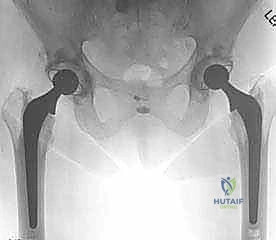

الخطوة الثالثة: تحضير وزرع الكوب الحُقي (Acetabular Component)

في جراحة الورك الإسمنتية الكلية، يتم استخدام كوب مصنوع من البولي إيثيلين عالي الكثافة (بلاستيك طبي شديد التحمل). يتم وضع طبقة من الإسمنت العظمي داخل التجويف الحُقي، ثم يُضغط الكوب البلاستيكي بقوة في الزاوية الميكانيكية الصحيحة. يتصلب الإسمنت خلال دقائق ليصبح جزءاً لا يتجزأ من الحوض.

الخطوة الرابعه: تحضير القناة الفخذية وزرع الساق المعدنية (Femoral Stem)

يتم استخدام مبارد جراحية خاصة لتجويف وتشكيل القناة الداخلية لعظمة الفخذ. بعد تنظيف القناة وتجفيفها، يتم حقن الإسمنت العظمي السائل داخل القناة الفخذية. فوراً، يقوم الدكتور هطيف بإدخال الساق المعدنية (Stem) المصنوعة من سبائك التيتانيوم أو الكوبالت كروم داخل القناة المملوءة بالإسمنت. يتم تثبيت الساق في الموضع الدقيق حتى يتصلب الإسمنت تماماً، مانعاً أي حركة دقيقة مستقبلاً.

الخطوة الخامسة: تركيب الرأس الكروي والاختبار

يتم تركيب رأس كروي جديد (مصنوع من السيراميك أو المعدن) على الجزء العلوي من الساق المعدنية. يقوم الجراح بإرجاع المفصل (رد المفصل) إلى مكانه واختبار نطاق الحركة بدقة، والتأكد من استقرار المفصل وتساوي طول الساقين.